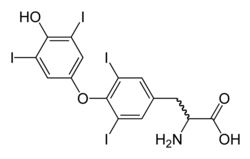

| Molecular structure of thyroxine, which is deficient in hypothyroidism | |